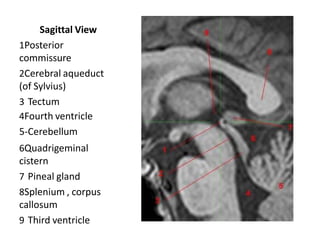

Sagittal View

1Posterior

commissure

2Cerebral aqueduct

(of Sylvius)

3 Tectum

4Fourth ventricle

5-Cerebellum

6Quadrigeminal

cistern

7 Pineal gland

8Splenium , corpus

callosum

9 Third ventricle